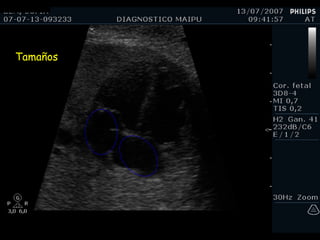

Tamaño